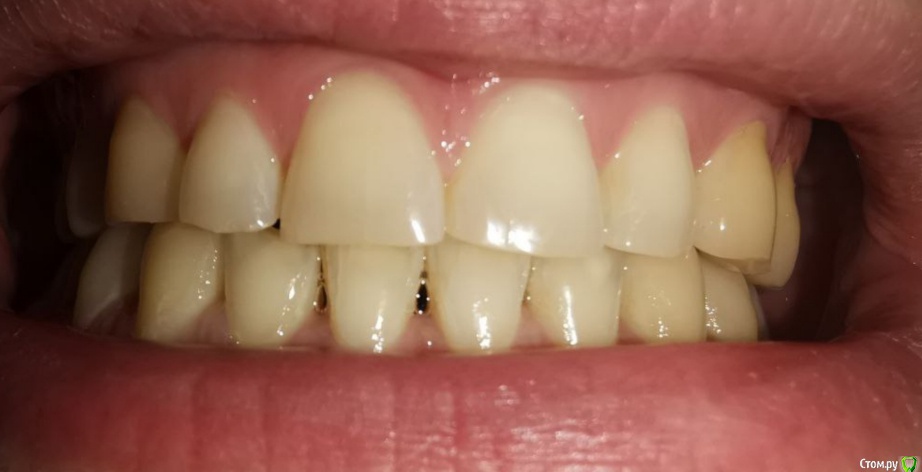

Мне 30 лет, лет 5 назад стоматолог-терапевт заметил излишнюю стираемость, была долгая эпопея с ортодонтическим лечением и вот наконец в прошлом месяце сняли брекеты и теперь настало время ортопедического.

Врач, который работает в паре с ортодонтом настаивает на полном протезировании (спереди виниры emax, сзади накладки так же из керамики). Со слов врача после диагностики сустава стало понятно, что чем выше поднимем прикус тем лучше, так должен уйти бруксизм, который сейчас присутствует.

Альтернативное мнение, которые я получил, что можно сделать накладки только на 5/6/7 со всех сторон, восстановить клыки композитом для "клыкового ведения" и пока все - полное протезирование всегда успеется. Может быть немного пожертвовав высотой прикуса.

По мнению первого врача, если делать только жевательные зубы выводя на нужную высоту прикуса, то передние зубы не сомкнутся и это нехорошо.

Эстетических хотелок у меня нет - только функциональные. Понимаю, что сделав полное протезирование с этой "иглы" уже не слезть и раз в какое-то времени придется рот целиком обновлять (в связи с возрастными изменениями).

п.с. На некоторых зубых есть временные накладки, которые делали на время отродонтического лечения.